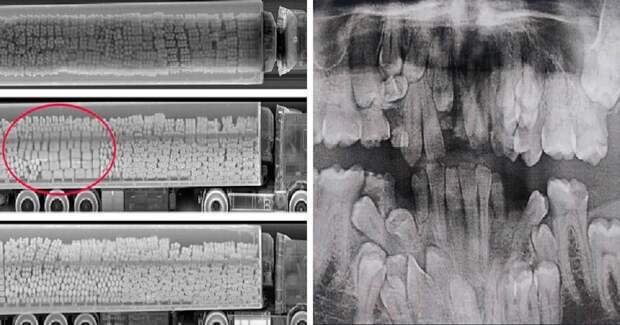

«У меня клейдокраниальный дизостоз, или, если проще, у меня в челюсти много лишних «запасных» зубов»

«Я дантист, но рентгеновские снимки детей 6-12 лет меня немного пугают до сих пор»

Так рентген помогает обнаружить контрабанду,